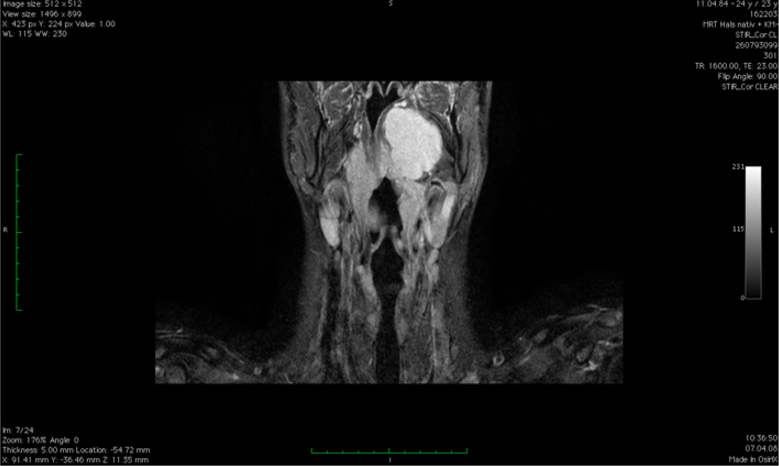

Karzinome der Speicheldrüse

Zu den Karzinomen der Speicheldrüsen gehören vor allem Azinuszellkarzinome, Mukoepidermoidkarzinome, adenoid-zystische Karzinome, Adenokarzinome und Karzinome in pleomorphen Adenomen sowie Plattenepithel- und undifferenzierte Karzinome.